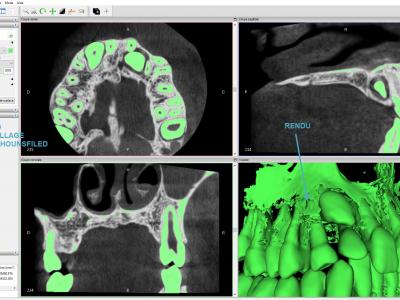

- Importer les fichiers DICOM dans Invesalius : il faut sélectionner le dossier avec toutes les images DICOM et les importer toutes

- Etape de seuillage : sélection d'un intervalle de densité (Unités Hounsfield) : par exemple 470 à 3000 pour os + dents, ou 1500 à 3000 pour les dents seules (situation qui nous intéressera dans ce cas).

Il est malheureusement quasiment impossible de sélectionner uniquement les dents sans avoir des éléments osseux. Il faut trouver le bon équilibre entre des surfaces dentaires et radiculaires nettes et le moins d'éléments osseux adjacents. Ces éléments osseux seront ensuite nettoyés dans Meshmixer.

Plusieurs itérations sont parfois nécessaires afin de trouver le meilleur équilibre.

- Créer la surface